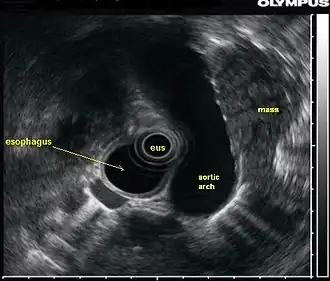

In this endoscopic ultrasound image, a mass (in this case, from lung cancer) is visualized using an ultrasound probe (EUS) inserted into the esophagus.

An endoscopic ultrasound probe placed in the esophagus can also be used to visualize lymph nodes in the chest surrounding the airways (bronchi), which is important for the staging of lung cancer. Ultrasound can also be performed with an endoscopic probe inside the bronchi themselves, a technique known as endobronchial ultrasound.